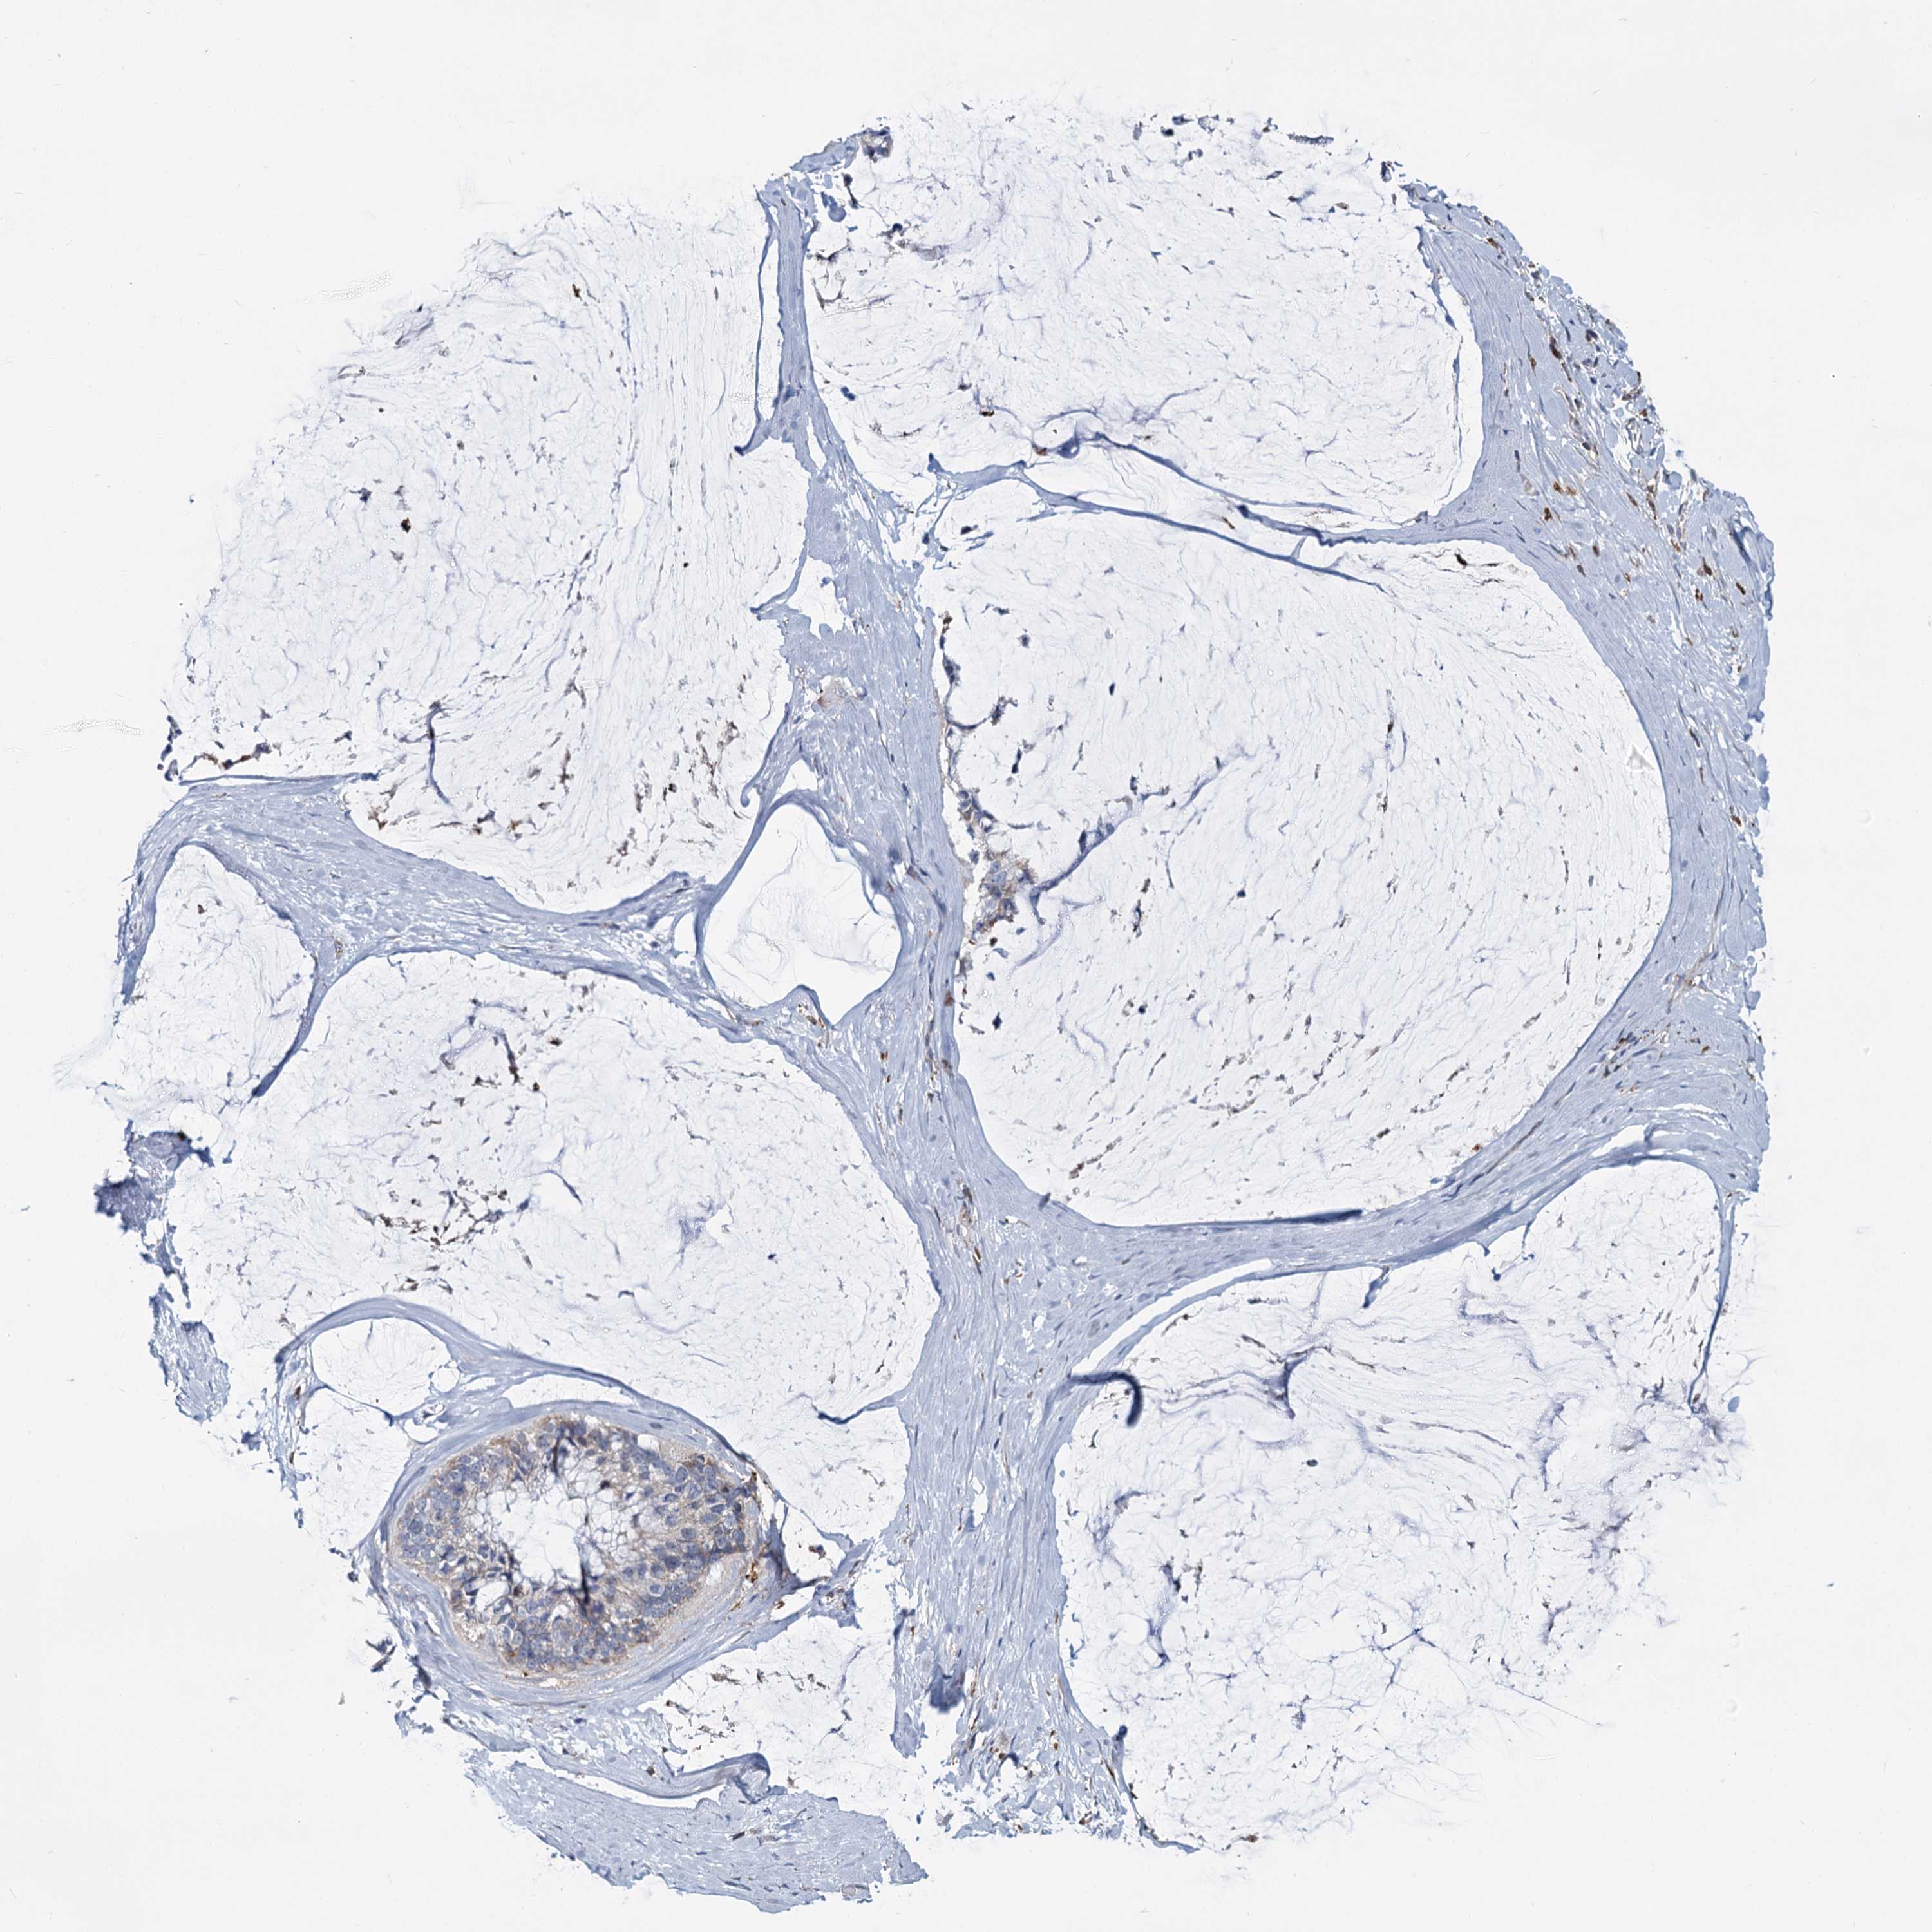

OVARIAN CANCER - Protein expressioni

A mouse-over function shows sample information and annotation data. Click on an image to view it in a full screen mode. Samples can be filtered based on level of antibody staining by selecting one or several of the following categories: high, medium, low and not detected. The assay and annotation is described here.

Note that samples used for immunohistochemistry by the Human Protein Atlas do not correspond to samples in the TCGA dataset.

Antibody stainingi

Antibody staining in the annotated cell types in the current human tissue is reported as not detected, low, medium, or high, based on conventional immunohistochemistry profiling in selected tissues. This score is based on the combination of the staining intensity and fraction of stained cells.

Each image is clickable and will lead to virtual microscopy that enables deeper exploration of all samples and also displays staining intensity scores, fraction scores and subcellular localization as well as patient and tissue information for each sample.

Antibody HPA039349

Staining

High

Medium

Low

Not detected

Intensity

Strong

Moderate

Weak

Negative

Quantity

>75%

75%-25%

<25%

None

Location

Nuclear

Cytoplasmic/membranous

Cytoplasmic/membranous,nuclear

Cystadenocarcinoma, serous, NOS

Carcinoma, endometroid

Cystadenocarcinoma, mucinous, NOS

Carcinoma, NOS